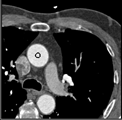

Samples for ascending aorta detection (black circle):

Cluster of candidate points in the ascending aorta.